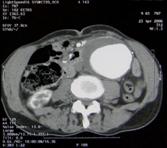

Additional diagnostic methods such as CT, MRI, and angiography may be used to plan treatment. These identify the size (the most critical factor in treatment), location, and relationships to surrounding organs. Angiography is not usually required for open surgery planning but is recommended for endovascular repair.